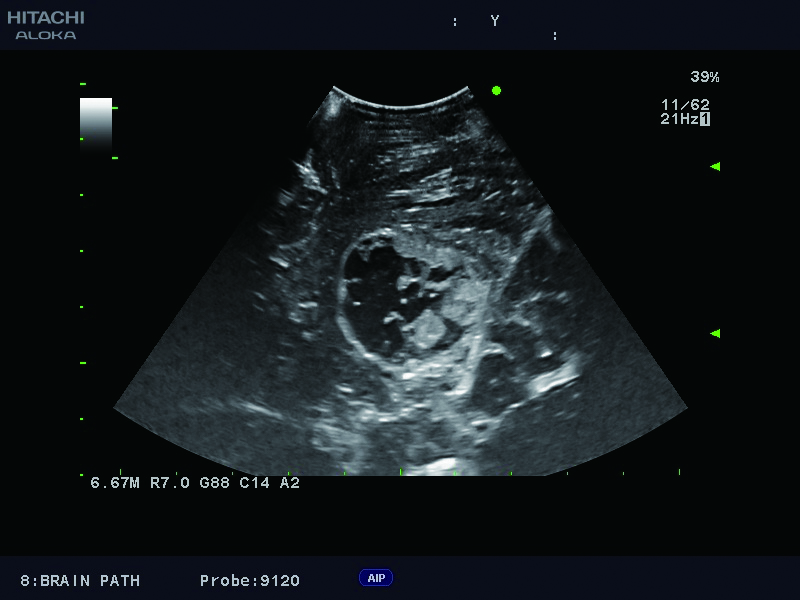

Superior guidance for all applications

Fujifilm Healthcare Americas is committed to designing tools that help surgeons navigate inside the human body and provide the necessary information to immediately make critical surgical decisions.

Fujifilm Healthcare's dedication to Surgeons provides outstanding ultrasound technology, professional support and the specialized tools necessary to best perform comprehensive real-time ultrasound imaging in Breast Surgery, General Surgery, Laparoscopic Surgery, Neurosurgery, Robotic Surgery and Surgical Oncology.

Imaging Clearly Defined

State-of-the-art digital architecture and advanced imaging features to redefine the capabilities of surgical ultrasound.